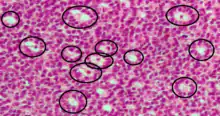

Call–Exner bodies, giving a follicle-like appearance, are small eosinophilic fluid-filled punched out spaces between granulosa cells.[1] The granulosa cells are usually arranged haphazardly around the space.

They are pathognomonic for granulosa cell tumors.

They are composed of membrane-packaged secretion of granulosa cells and have relations to the formation of liquor folliculi which are seen among closely arranged granulosa cells.